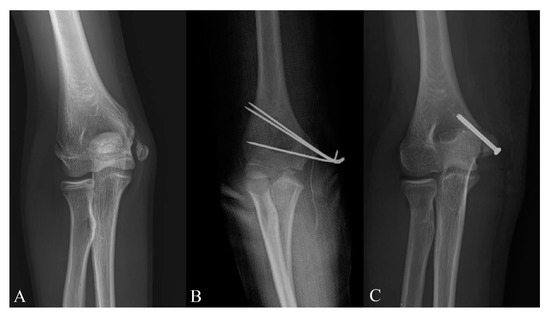

Is Computed Tomography Necessary for Diagnostic Workup in Displaced Pediatric Medial Epicondyle Fractures?

- Rickert, K.D.; Sarrel, K.L.; Sanders, J.S.; Jeffords, M.E.; Hughes, J.L.; Upasani, V.V.; Farnsworth, C.L.; Edmonds, E.W.; Pennock, A.T. Medial epicondyle fractures: Biomechanical evaluation and clinical comparison of 3 fixation methods used in pediatric patients. J. Pediatric Orthop. 2020, 40, 474–480. [Google Scholar] [CrossRef] [PubMed]